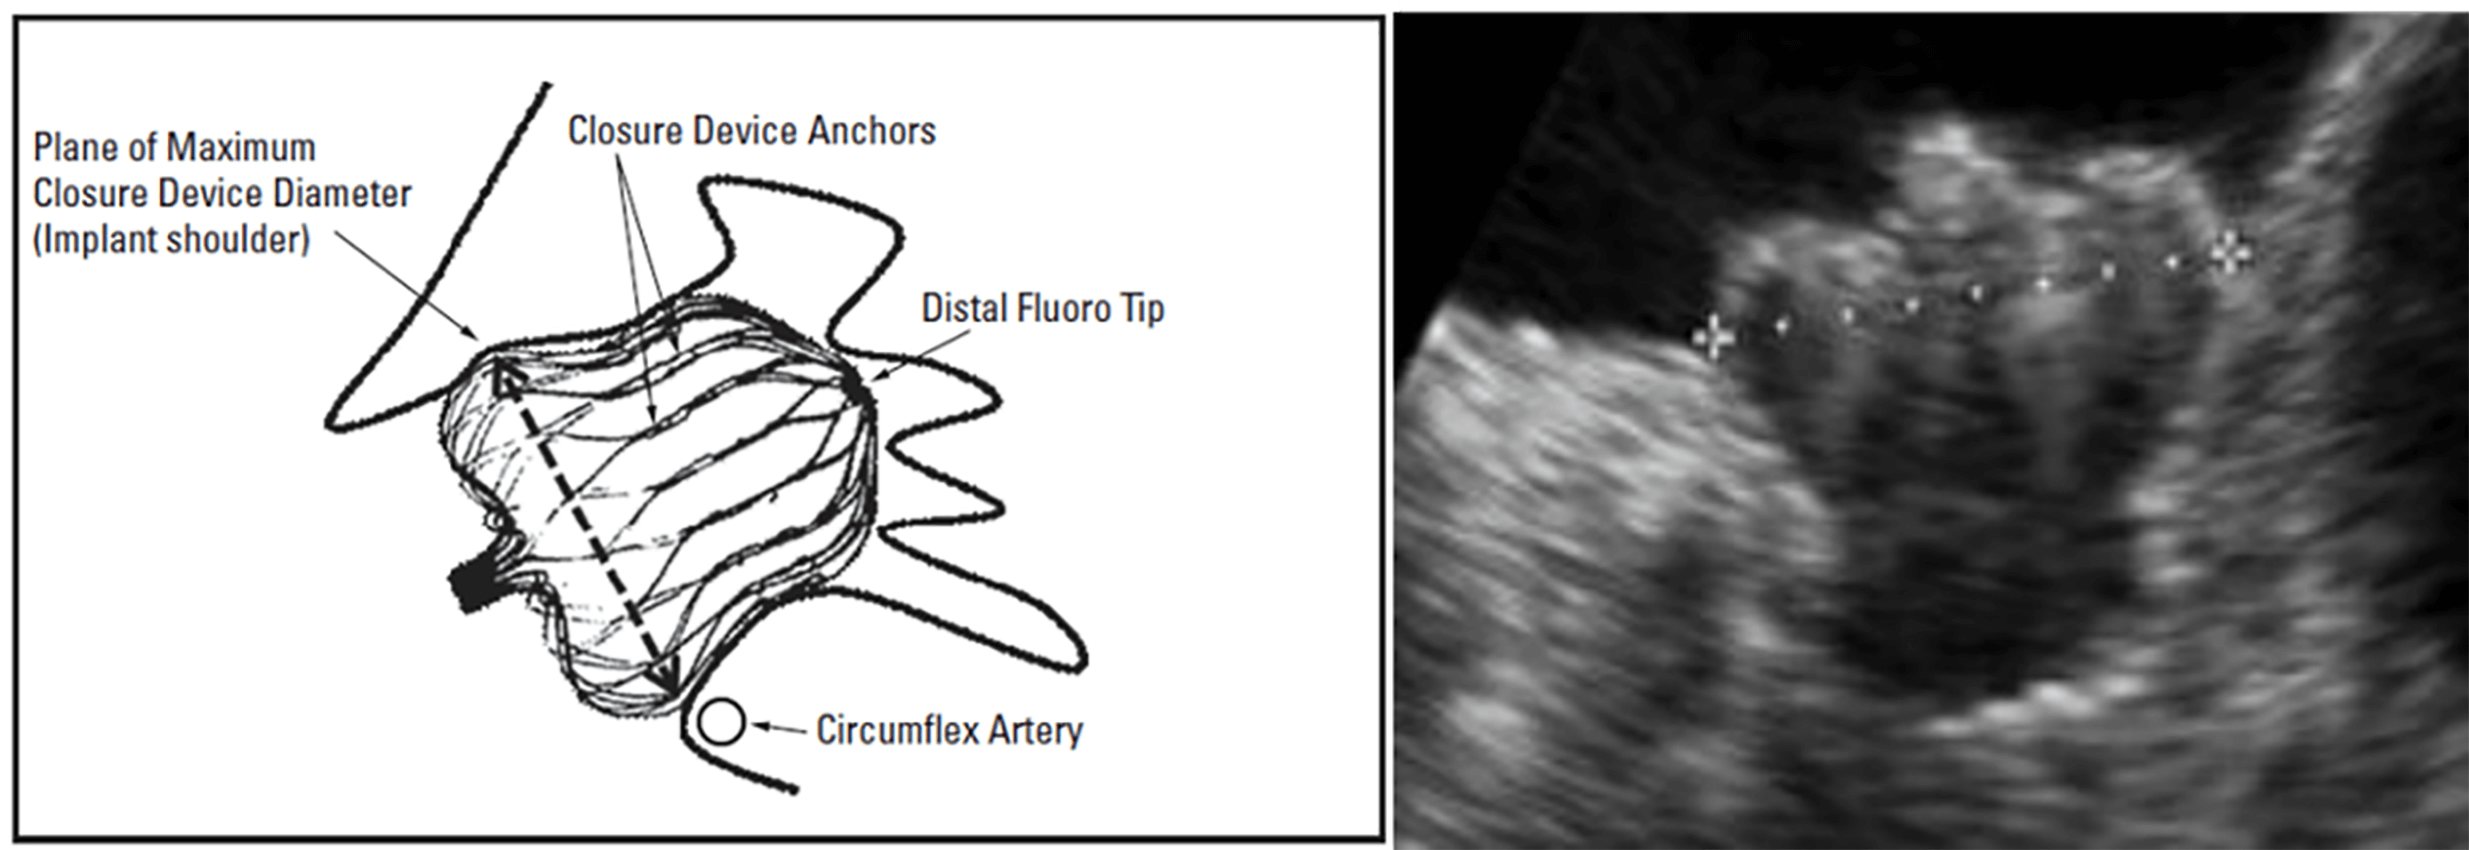

Because the Watchman FLX™ functions as an occlusive device, precise measurement of the landing zone and depth is critical for appropriate sizing. The landing zone is defined by a line drawn from the inferior aspect of the LAA at the level of the LCx to a point 1–2 cm distal to the ridge adjacent to the LSPV. The LAA depth is then measured perpendicularly from this line (Fig. 11) [17]. Device size selection follows the manufacturer’s recommended sizing and compression criteria (Fig. 12).

Fig. 11.

Measurement of the landing zone and depth of the left atrial appendage (LAA) for the Watchman FLX™ device. LCx, left circumflex artery.

Fig. 12.

Watchman FLX™ size selection is based on the diameter of the left atrial appendage (LAA) landing zone. The recommended compression range is 10%–30%. The required depth for device implantation may vary depending on the degree of compression (reproduced with permission from Boston Scientific).

Alignment of the distal tip of the device with the distal marker of the sheath (right arrow). At this stage, the device shoulder should ideally be positioned at the level of the left circumflex artery (LCx) (reproduced with permission from Boston Scientific).

Fig. 16.

The shoulder of the Watchman FLX™ device positioned at the level of the left circumflex artery (LCx) (reproduced with permission from Boston Scientific).